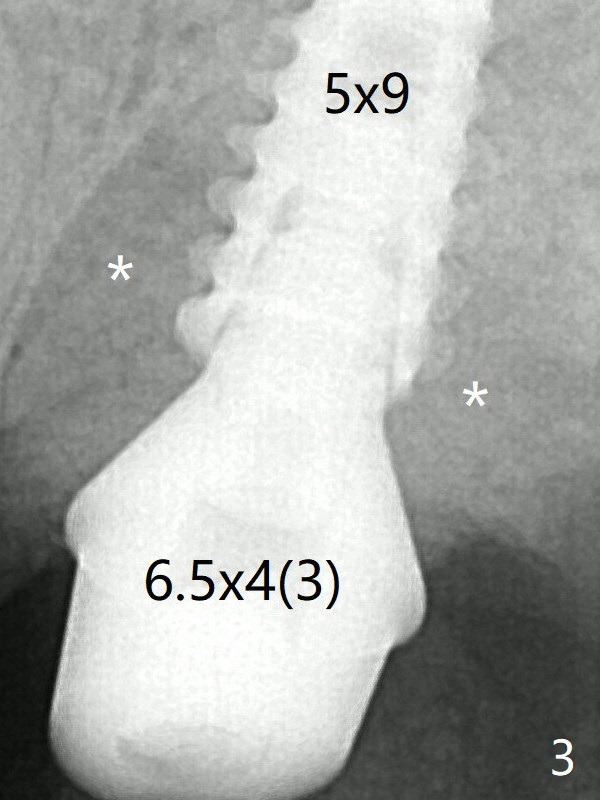

Since a 5x9 mm dummy implant is placed with stability, a definitive implant with the same dimension is chosen with >50 Ncm (Fig.3).  Prior to and after abutment placement, Vera graft is placed (*).  The provisional perforates with loose abutment 3.5 months postop.  A 6x4 mm healing abutment is placed.  Osteointegration occurs 4 months postop (Fig.6).